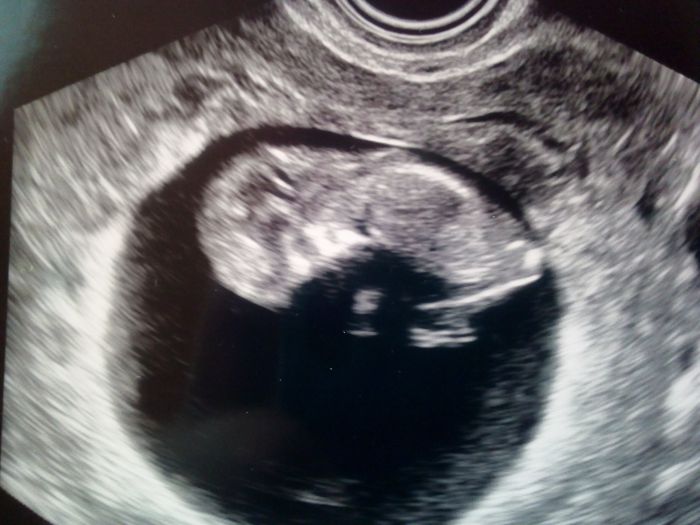

[1129323]krasny Zelvik

U nas dnes kontrola, vse v poradku. Minule jsem si a dr asi nerozumela, mame 4,5 cm

Juuu krása! A ty tlapičky!

to máme prcky podobně veliké